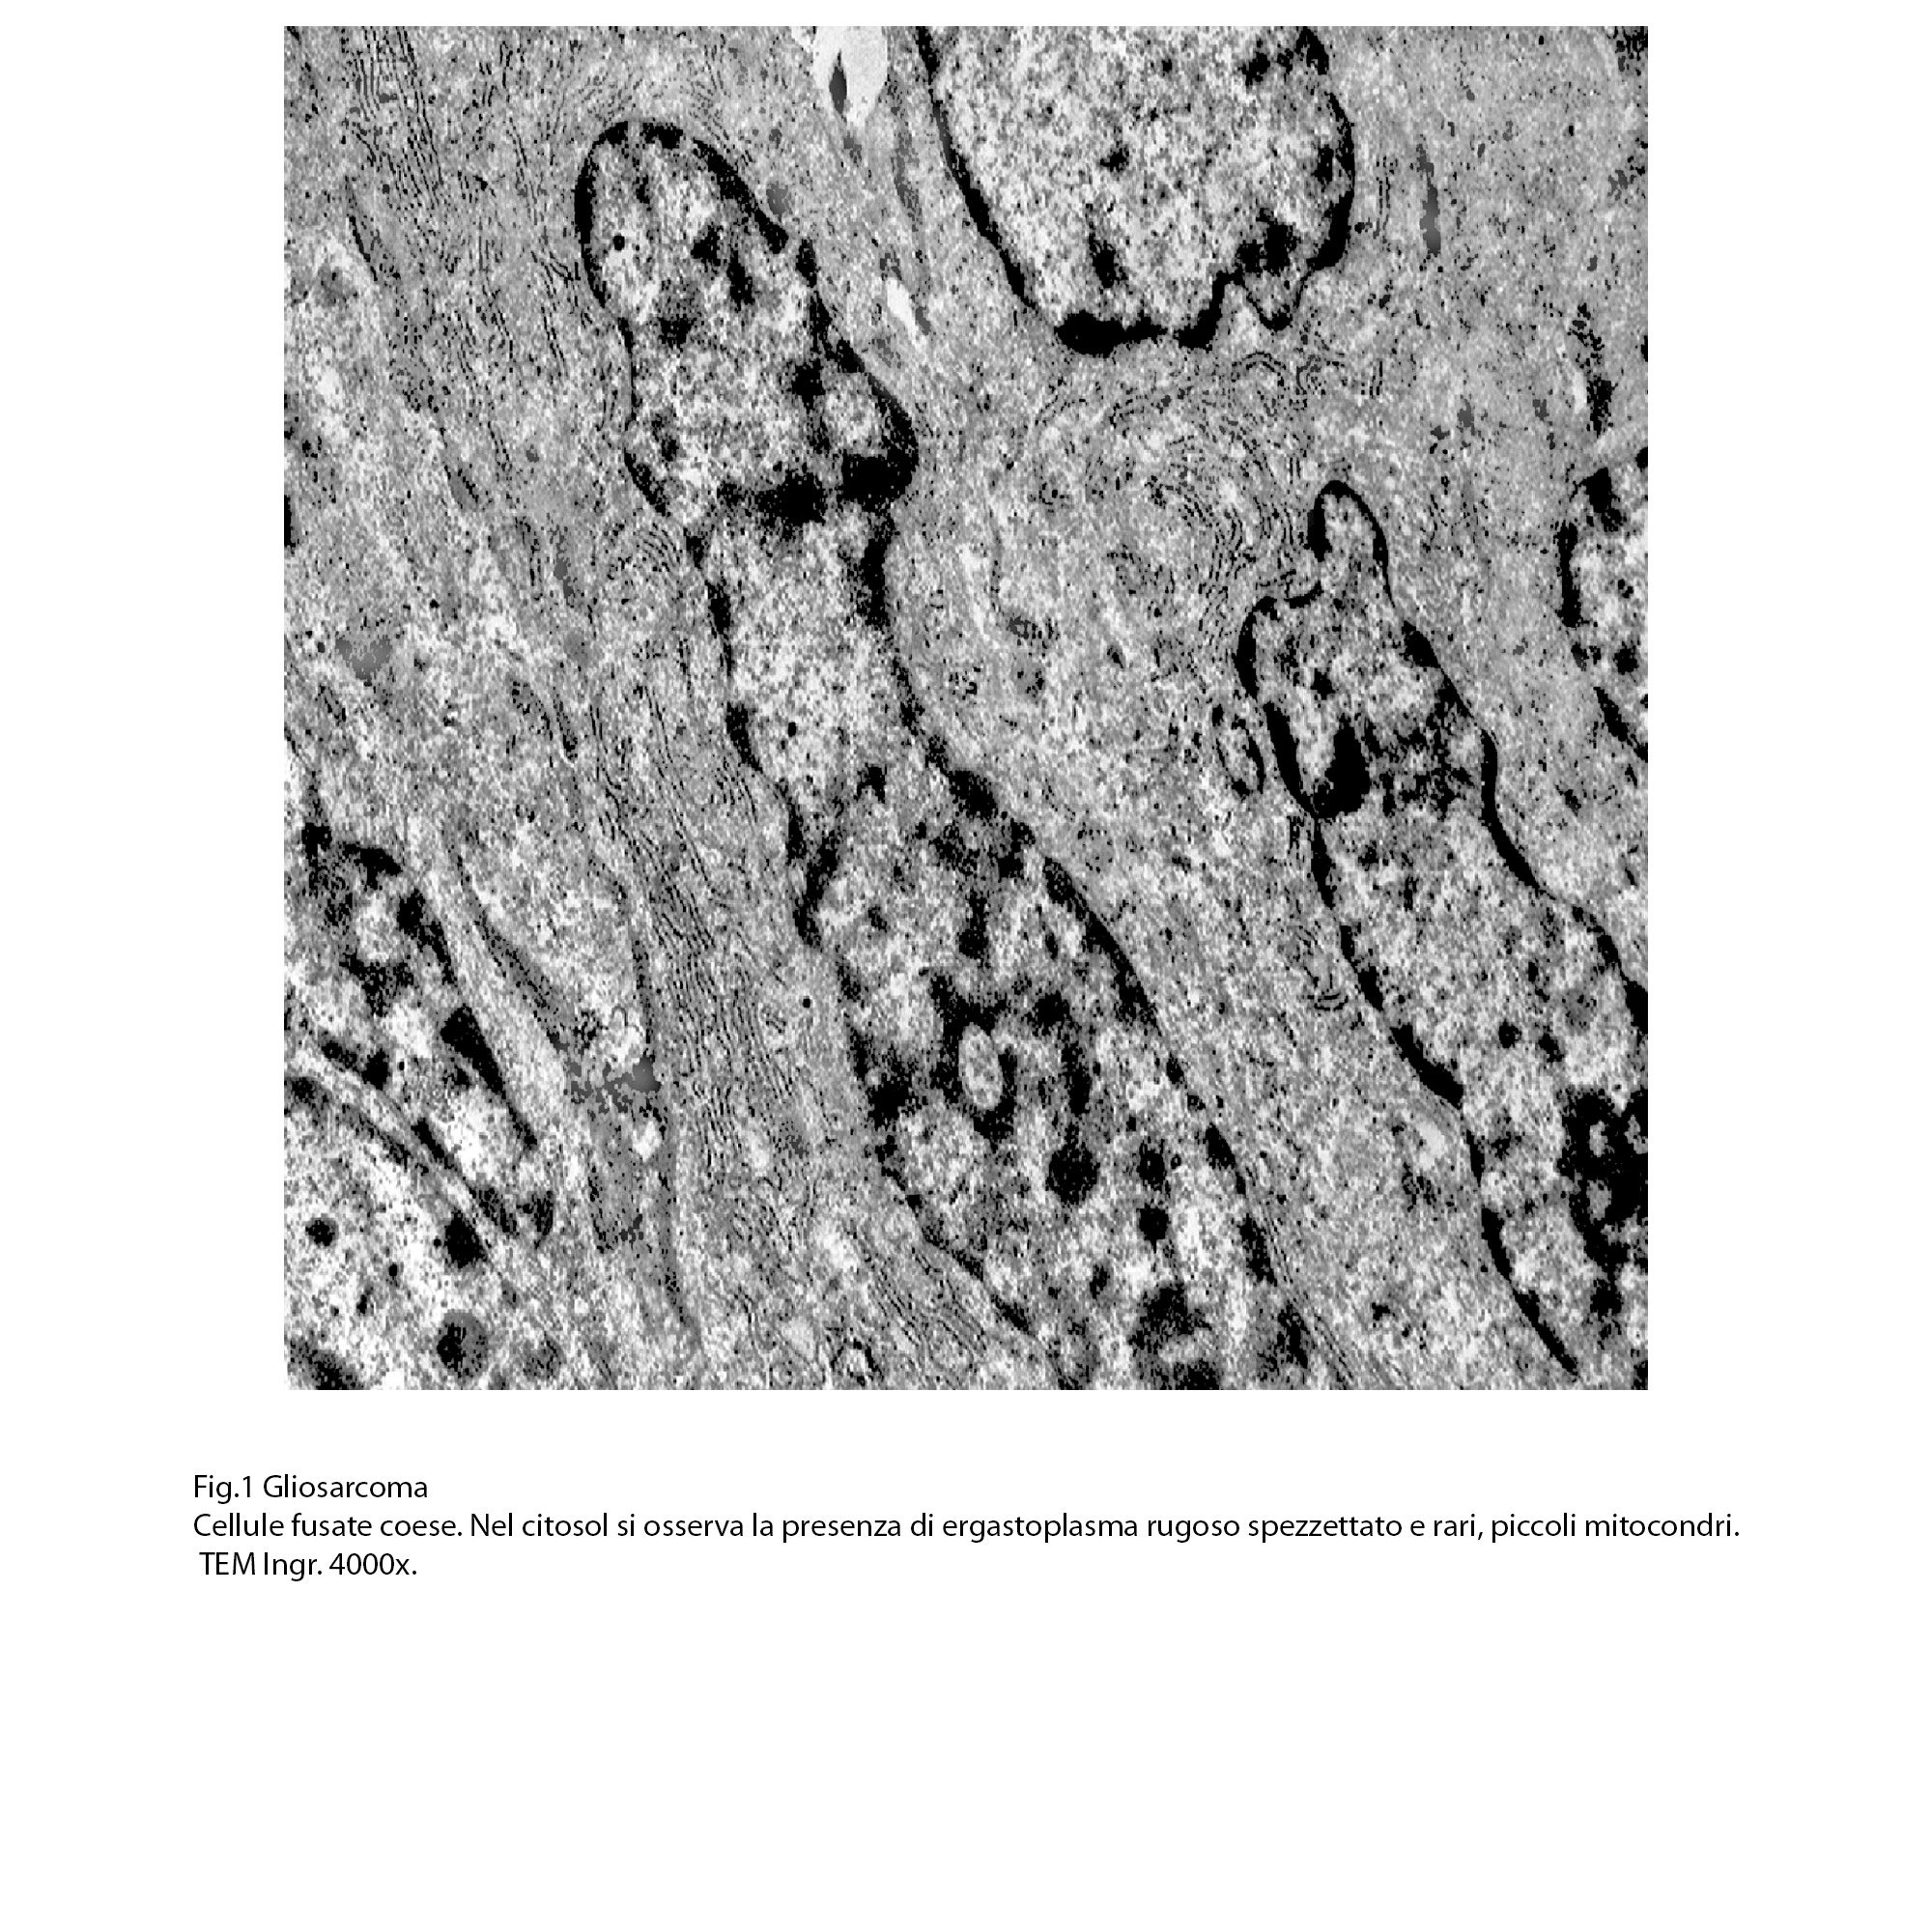

Fig.1  Fig.2

Fig.2  Fig.3